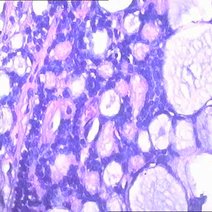

囊肿是什么

囊肿是指长于身体的某个器官囊状的良性包块,囊内容物通常是不同性质的液体,通俗的说囊肿就是囊袋内包裹的液体东西,用手触摸时有柔软的感觉。其形成的原因大多数...79020人收听